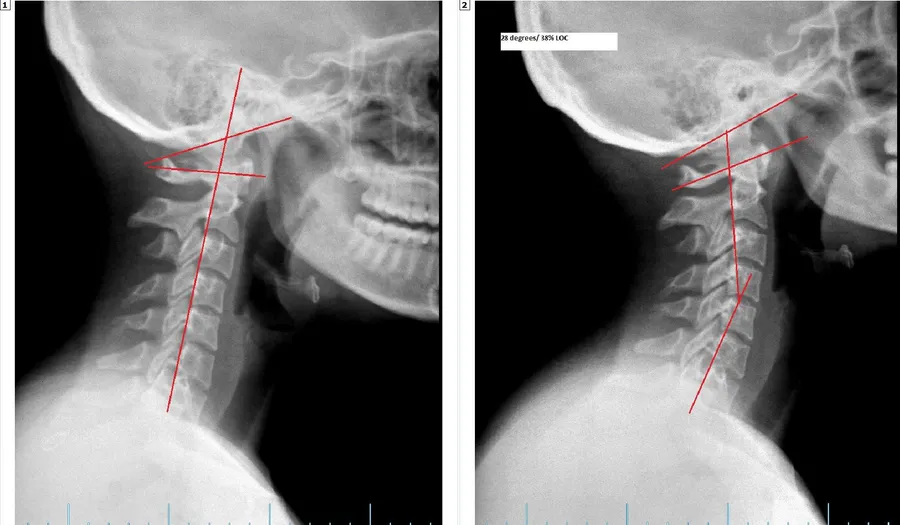

When the spine is well aligned, there is little to no nerve stress and the body is able to function optimally. Some times through physicals stresses such as motor vehicle accidents, slips and falls, sports injuries, and other traumas.  The spine can get misaligned and put pressure on the nervous system affecting the way that the body functions. Our job as doctors is to find out where the interference is and reduce it through Chiropractic Adjustments.  Objectively we can document where the problem is and then measure our patients progress as they go through the rehabilitation process.  Below is a series of before and after X-Rays of some our patients.

BEFORE AFTER

RESTORING THE CERVICAL CURVE AFTER A WHIPLASH INJURY